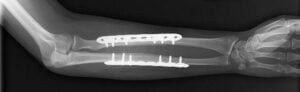

If there are multiple fragments of bone, the bone is displaced, or both bones are fractured, surgical treatment is needed. In the case of an open fracture, where the broken bone has punctured the skin, surgery is performed as soon as possible to limit the risk of further injury. The goal of surgery is to realign the bones and provide stabilization so that the bones can heal in the proper position.

Open reduction and internal fixation: An incision is made to expose the fracture. The bones can be stabilized by metal plates and screws applied to the surface of the bones bridging the point of the fracture or a rod placed lengthwise down the center or marrow portion of the bone.

When plates, screws or rods are used for internal fixation, they can be left in the arm indefinitely. In some cases, surgery to remove some or all of the hardware is done after the fracture has healed if there is pain from the metal implants or if they are prominent under the skin.

While we don’t know whether it was one or both of the forearm bones that were fractured, the more common scenario is that both bones were involved. There was no evidence of an open fracture, so the overwhelming likelihood is that Washington underwent an open fixation with plates and screws, rather than a rod placement or external fixator.